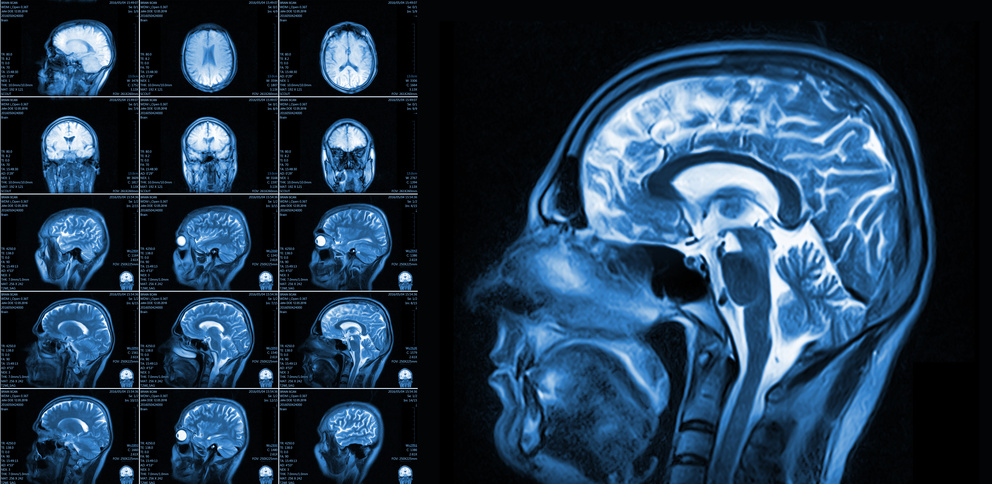

Neurodevelopmental disabilities, including autism, attention-deficit hyperactivity disorder, dyslexia, and other cognitive impairments, affect millions of children worldwide, and some diagnoses seem to be increasing in frequency. Industrial chemicals that injure the developing brain are among the known causes for this rise in prevalence.